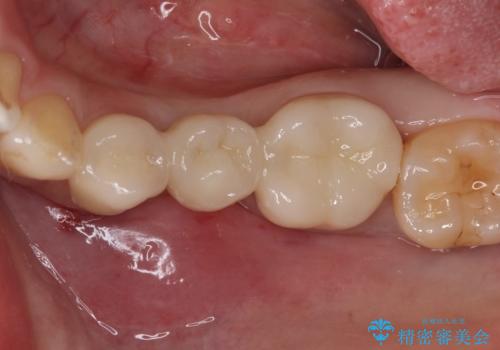

奥歯が痛い。乳歯を抜歯し、ブリッジによる咬合回復。

インプラントは希望されなかったため、ブリッジにて治療を行っております。

欠損補綴に対し、インプラントは有効な手段ですが比較的高額で、手術を伴います。

患者様によってはブリッジを選択される方もいらっしゃいます。